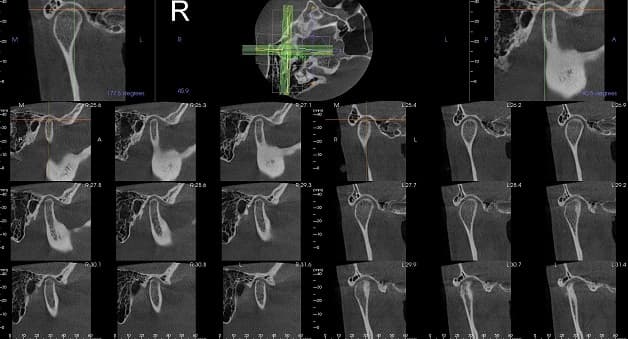

Cấu tạo của máy CT gồm một bóng phát tia X và bộ phận thu nhận tín hiệu, được đặt trong một khoang máy hình tròn. Hai bộ phận này ở vị trí đối diện nhau giúp chùm tia X có thể quay quanh cơ thể bệnh nhân.

Khi máy chạy, chùm tia X phát ra từ bóng sẽ xuyên qua một phần cơ thể theo chiều ngang và được tiếp nhận bởi bộ phận thu nhận tín hiệu. Sau đó, hệ thống máy tính sẽ biến đổi các thông tin lượng hóa thành hình ảnh 2D hoặc 3D của vị trí cần chụp.

Các bộ phận của cơ thể có mức độ cản tia nhiều như xương, răng, sỏi, máu xuất huyết…sẽ có màu trắng. Vùng cản tia ít như mỡ, dịch, phổi, khí… sẽ có màu tối.

Dựa vào hình ảnh được hiển thị trên phim, các bác sĩ có thể xác định những bất thường tại cơ quan được chụp.